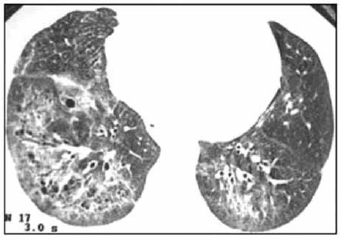

Mulher, 46 anos, procura atendimento médico com queixa de sensação de fraqueza e adinamia. Observou que, principalmente em dias mais frios, apresenta palidez e cianose em extremidades. Além disso, já procurou dermatologista por queda de cabelo, além de espessamento e endurecimento da pele. Houve surgimento de diversas lesões de pele com características de teleangiectasias e, recentemente, passou a cursar com disfagia a alimentos sólidos e dispneia aos pequenos esforços. O ecocardiograma transtorácico revelou PSAP de 70 mmHg, e um corte da tomografia de tórax realizada está ilustrado a seguir.